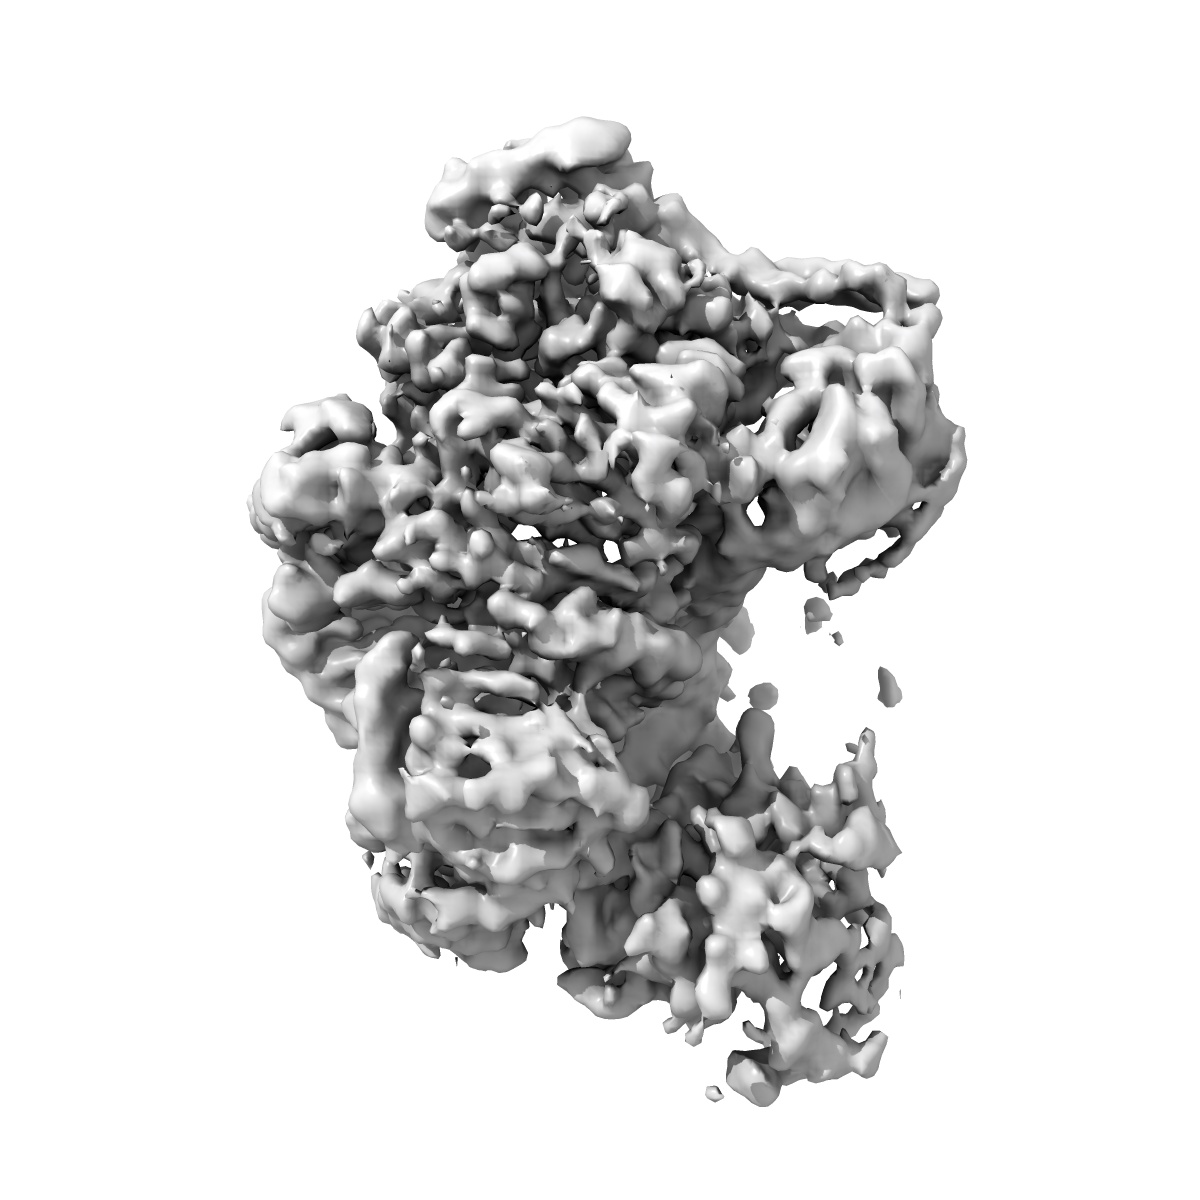

EMD-48721

Cryo-EM Structure of HIV-1 Reverse Transcriptase p66 tetramer in Complex with 5-{2-[2-(2-oxo-4-sulfanylidene-3,4-dihydropyrimidin-1(2H)-yl)ethoxy]phenoxy}naphthalene-2-carbonitrile (JLJ648), a Non-nucleoside Inhibitor

Single-particle3.43 Å

Fitted models: 9mxt